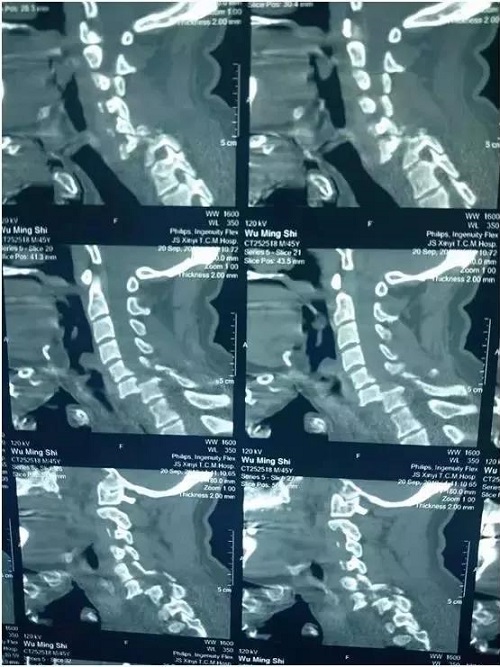

患者的术前CT

山东省立医院中心院区创伤骨科主任医师王鲁博对患者严格检查后,发现患者颈椎6/7节段虽然是极为罕见的完全脱位,但脊髓损伤属不完全性,意味着手术后有50%可能恢复站立行走。对手术医师来说,既要达到恢复颈椎序列和坚强稳定颈椎的目的,又要保证手术过程中不加重脊髓损伤,这是一个极严峻考验,医生要承担极大的心理压力。